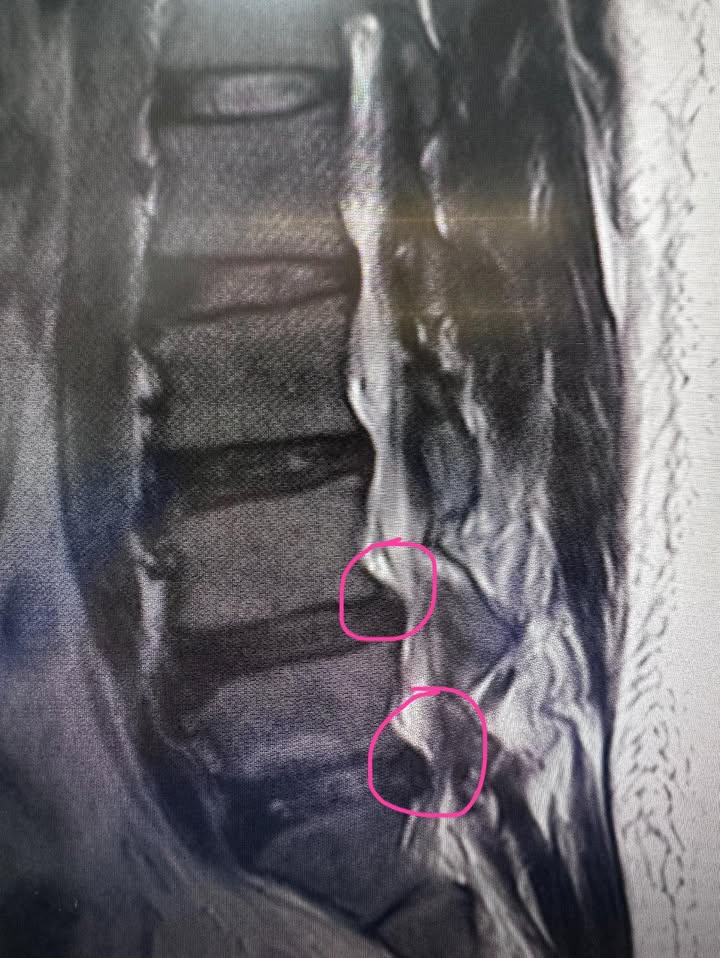

Cervical Spine Treatment Cases 精彩回顧 診所營業時間異動公告 2024.12.05 人生突然有了新的夢想 2024.12.09 2024.12.09 2024.12.09 腰椎疼痛三年原來是椎管狹窄合併突出 2024.12.11 頸椎壓迫與灑鹽動作的關係 2024.12.12 老臣無力可回天 2024.12.12 2024.12.13 2024.12.17 2024.12.18 2024.12.20 新店區黃先生命運逆轉勝治療紀實 2024.12.24 失散多年的表弟居然來找我治療 2024.12.25 跨海萬里從矽谷到台北的國際醫療外交 2024.12.25 痛起來要人命的腰椎滑脫卡壓神經根醫案 2024.12.26 ← 上一頁 26 27 28 29 30 下一頁 →